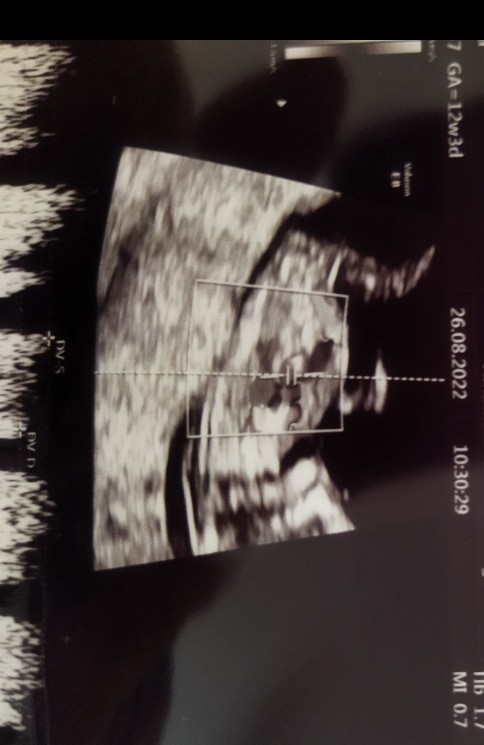

GratulacjeDziewczyny ja już po prenatalnych, wszystko dobrzekolejny chłopak będzie na grupie na 80%, już ma ponad 7cm i rośnie jak na drożdżach

Lekarzem nie jestem ale nie widzę na tym zdjęciu płciHej. Ja juz tak nie rzygam jak kot, ale adal się mega czuje do bani. Na prenatalnym wszystko ok. Dzidzia wzgledem usg poprzednich jeden dzien mniejsza, mam nadzieję, ze znow bedzoe drobna dziewczynka. Plci mi nie powiedział, mowil, zeza szybko. Teraz jestem 9 dni sama z dziecmi to bedzie lipa. Widzicie tu cokolwiek odnosnie płci?